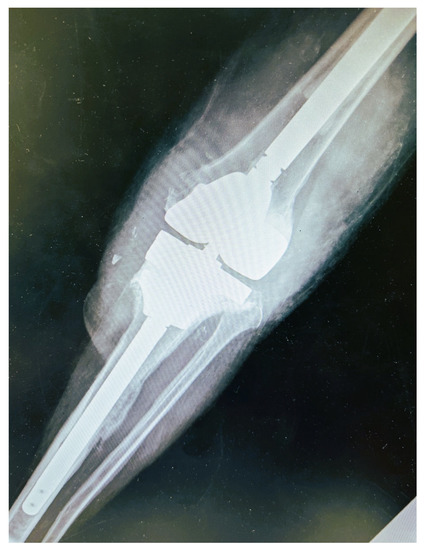

2. Case Presentation